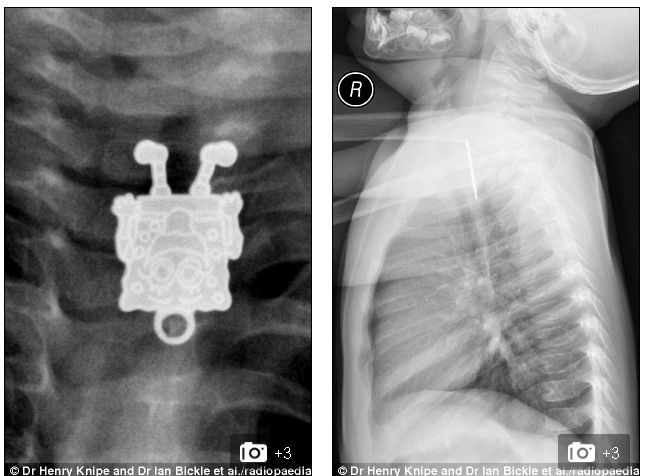

異物を飲み込んだ乳児をレントゲンしたら「スポンジボブ」が映ったと話題に|面白ニュース 秒刊SUNDAY

1歳4ヶ月の子供がペンダントを飲んでしまった

急いで病院に連れて行きレントゲン写真をとってみると・・・

> スポンジボブ <

もちろんこの乳児から異物は取り出され、無事退院した